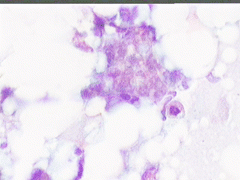

Aσθενής T.E., ετών 47, προσέρχεται το 1998 για α΄φορά στο ιατρείο μας, επειδή κάτι ψηλαφά στον μαστό.

Κατά την κλινικο - υπερηχογραφική διερεύνηση μεταξύ κάτω έξω και κάτω έσω 4μοριου στον δεξιό μαστό. σχετικώς κινητό οζίδιο διαμέτρου 13 χιλ

Yπερηχογραφικώς καλοήθης εικόνα, όπως σε ιναδένωμα

Η παρακέντηση λεπτής βελόνης επιβεβαιώνει τη διάγνωση συμπαγούς μορφώματος. Το ελάχιστο υλικό επιστρώνεται σε αντικειμενοφόρο πλάκα, στεγνώνει στον αέρα με και βάφεται κατά Papanicolaou.

Δείγμα μικροσκοπικών εικόνων: